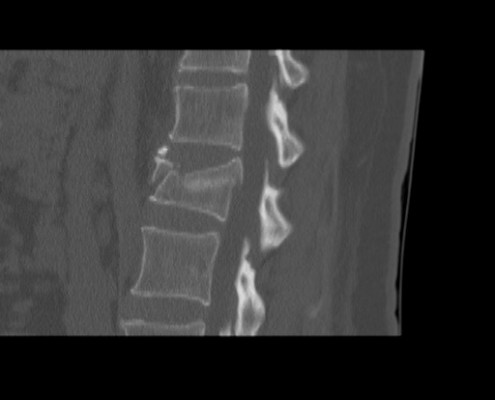

Puedes ver imágenes de una fractura y de la técnica quirúrgica de un caso real del 2015 tras este texto.